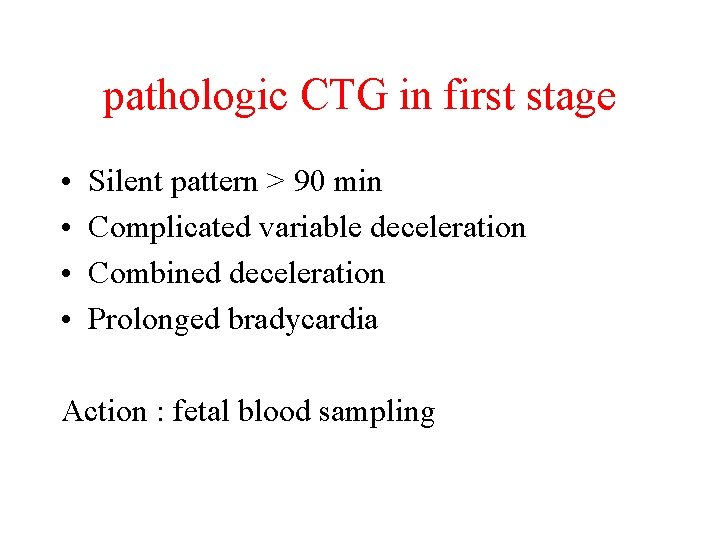

pathologic CTG in first stage • • Silent pattern > 90 min Complicated variable deceleration Combined deceleration Prolonged bradycardia Action : fetal blood sampling